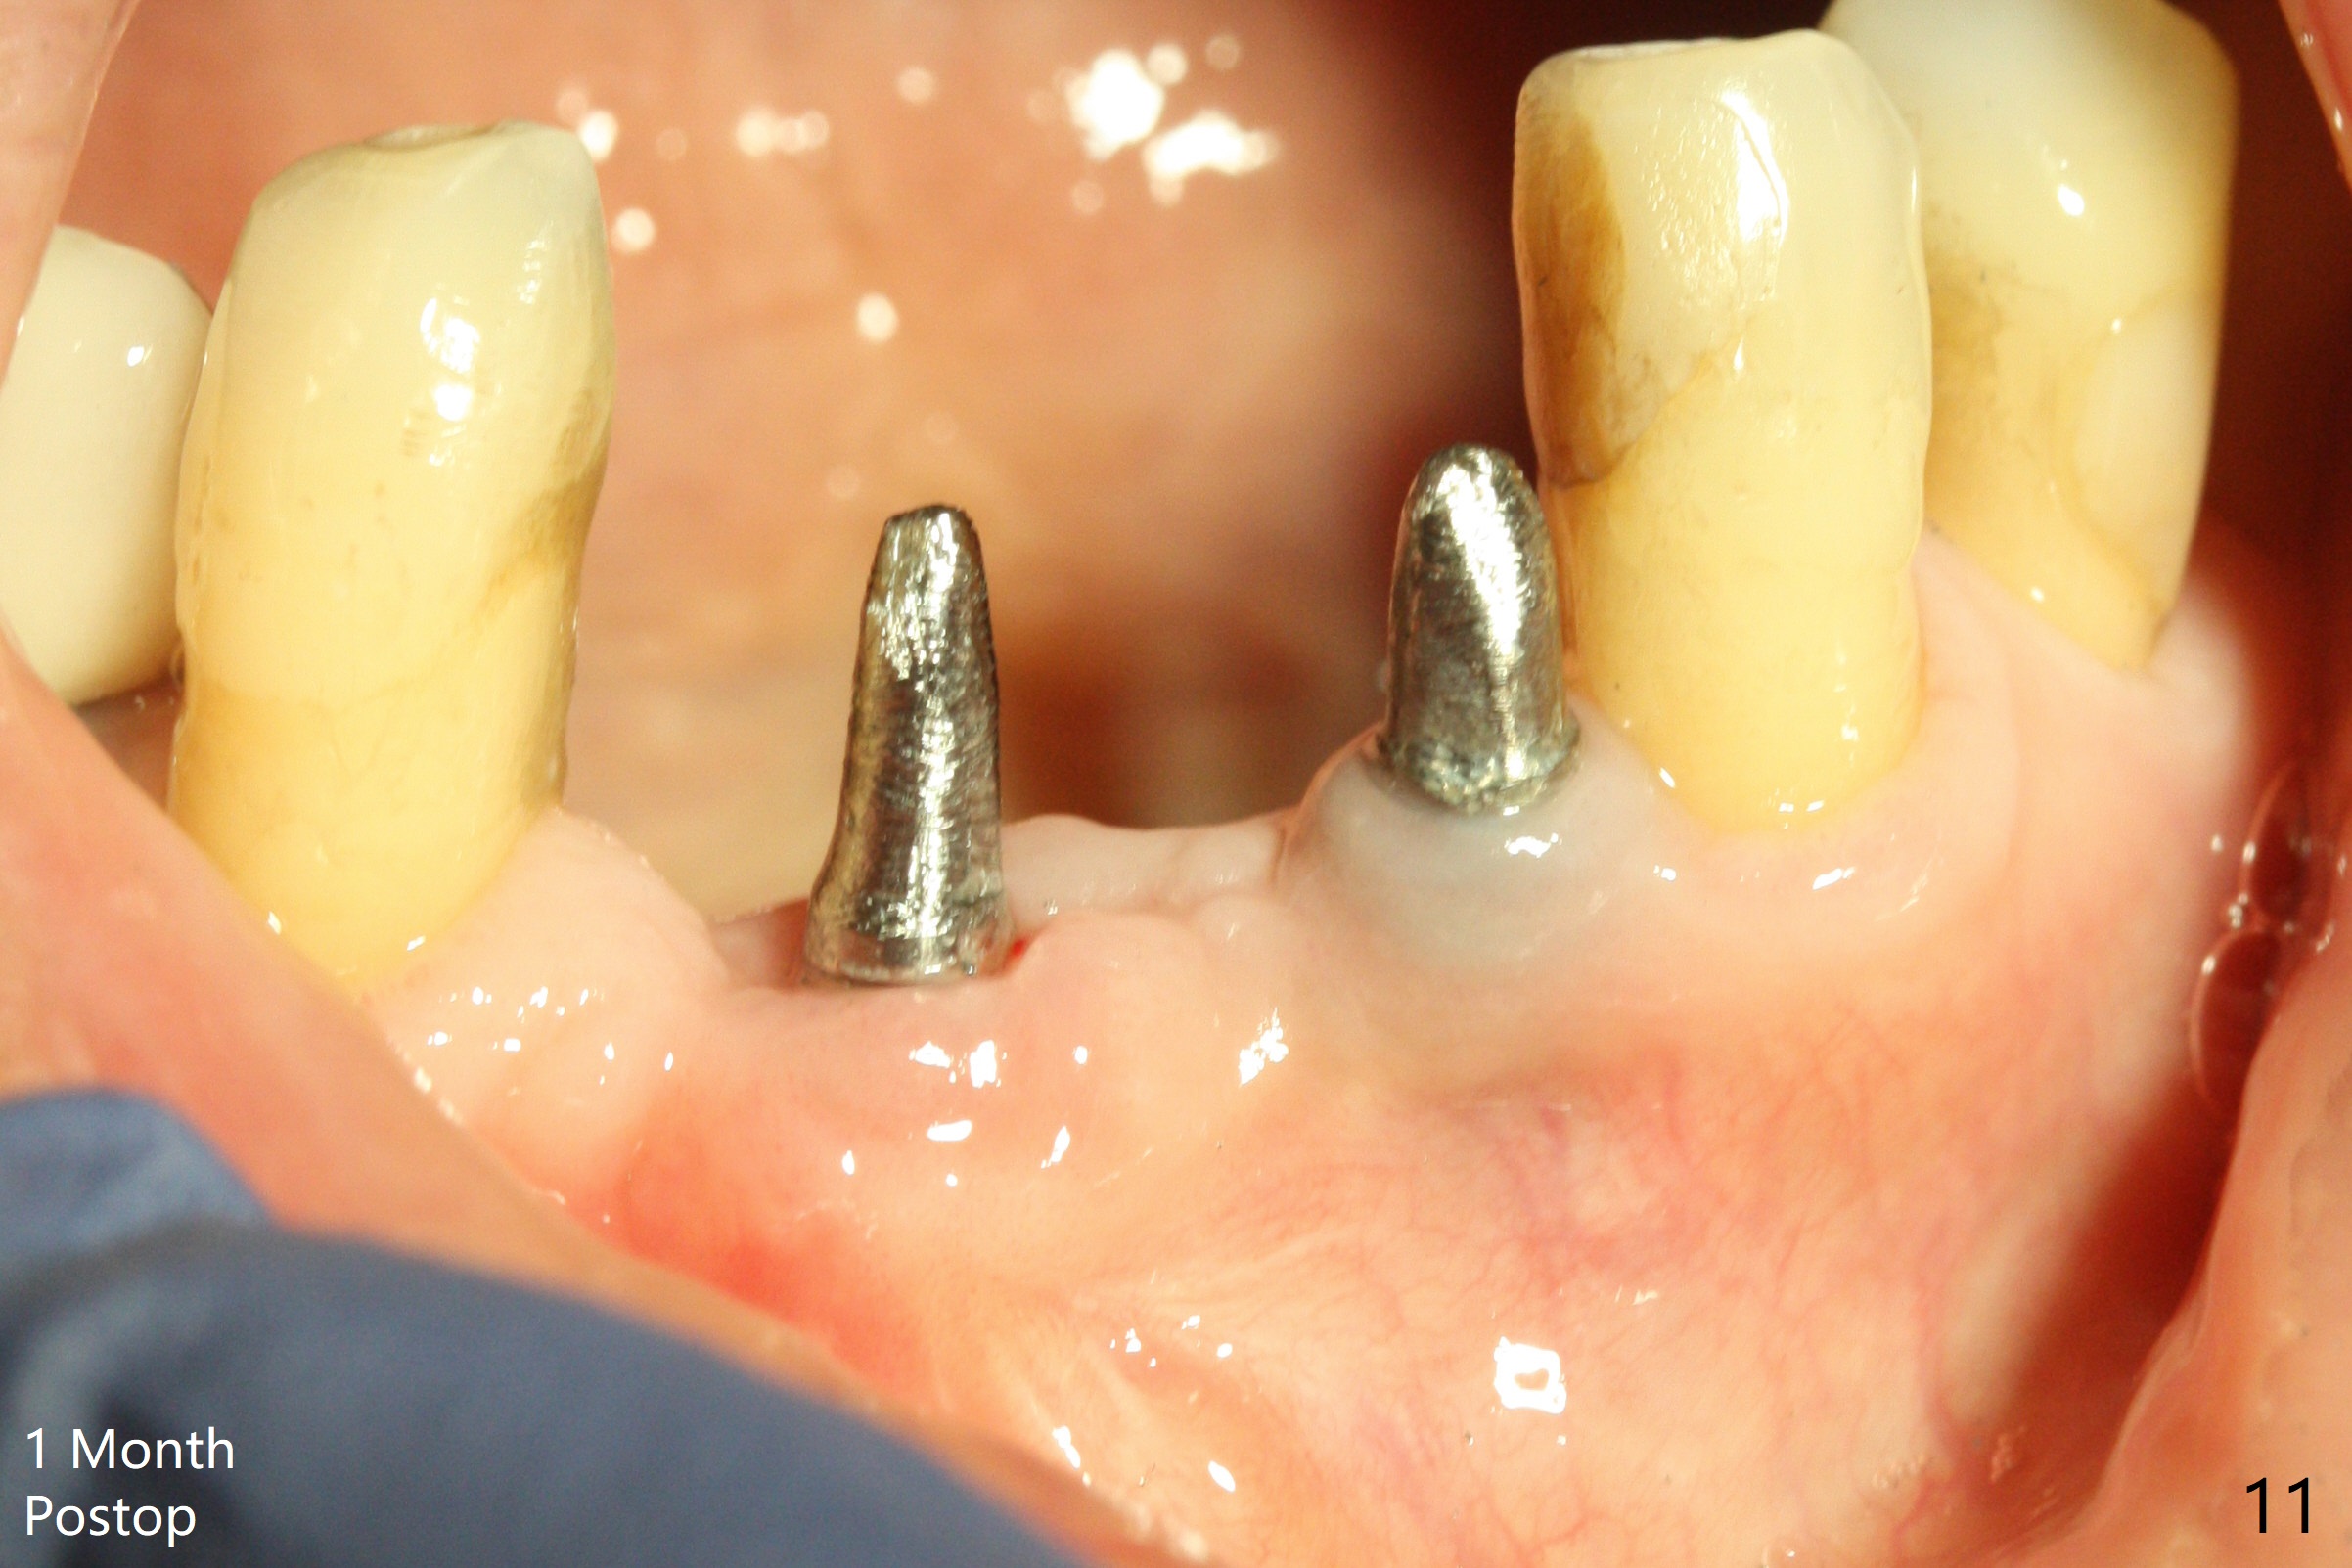

The wound at #25 seems to heal 1 month postop; after prep (Fig.10,11), a provisional FPD is fabricated. Impression is taken for surgical guides of UL and LL implants. The patient requests early final restoration (Fig.12). The small implant placed lingually (Fig.12 *, 2 mm) is associated with the pleasing gingiva in color, as compared to the 3 mm one at #23 with the metal shaded gingiva.